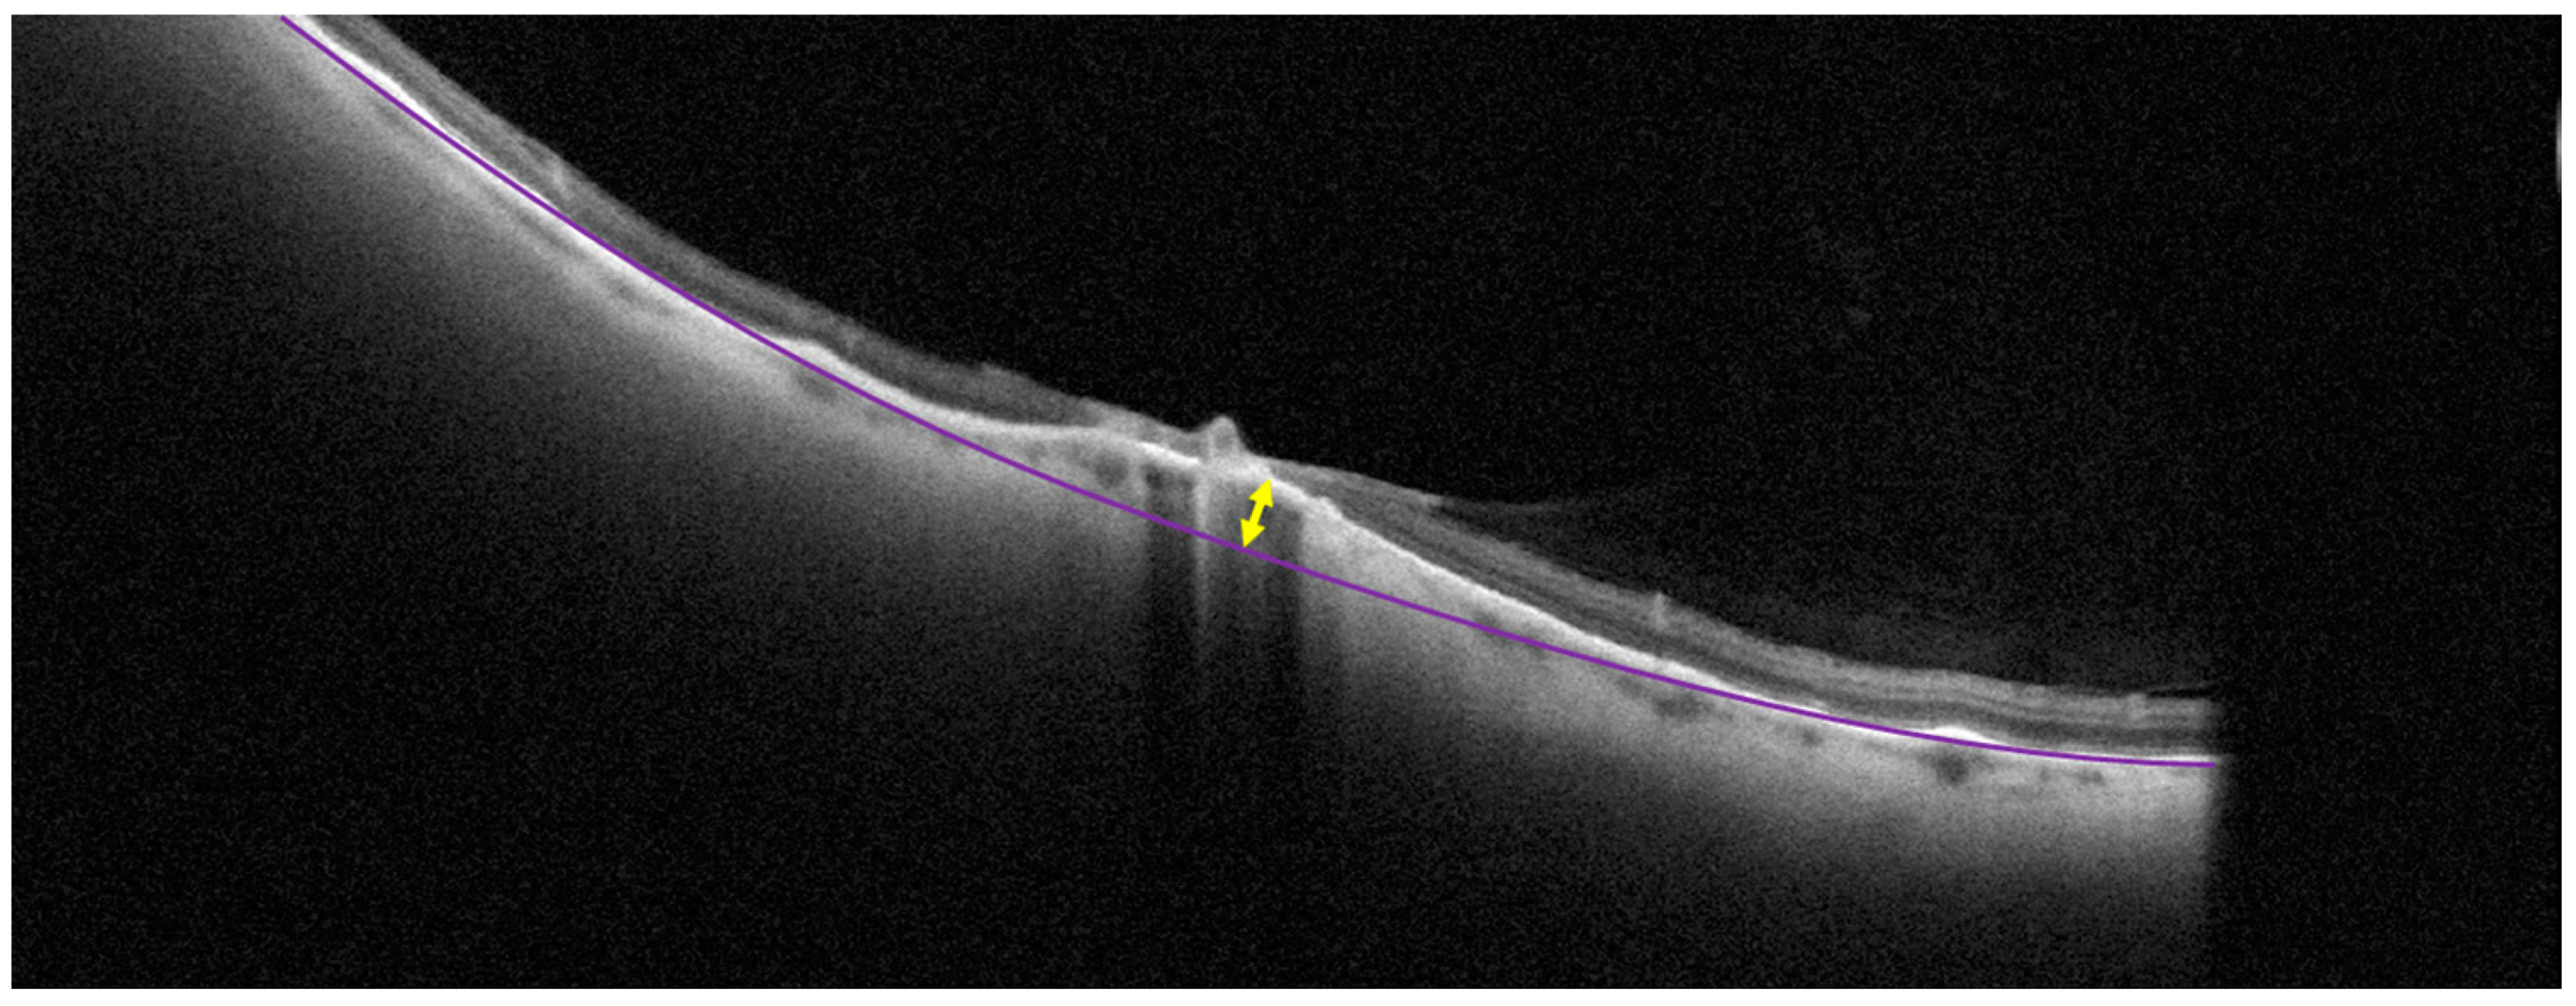

The height of the scleral indentation was measured using scans of the lesion across and along its greatest dimension. The measurements were performed in ImageJ 1.53k (NIH, Bethesda, CA, USA). To measure the height of the scleral indentation, first the line of the retinal pigment epithelium (RPE) was reconstructed based on the RPE line along with the lesion area using an ellipsoid curve. Next, the distance between the highest point of the actual RPE line and the reconstructed line beneath it was measured (Figure 1).

Figure 1. Measurement of choroidal indentation on a cross-sectional optical coherence tomography scan. The purple line represents the level of retinal pigment epithelium. The yellow arrow shows the maximum scleral indentation in the middle of the lesion.